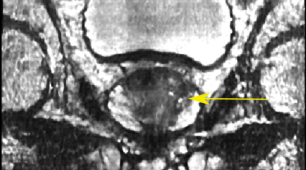

Fig. 4: SR result for anisotropic SRGAN using real data, yellow arrow indicates suspicious cancer region

Figure 4 is an example of axial and coronal views. The HR views portray the difference in resolution between the in-plane axial slice and the coronal and sagittal through-plane slices. The SR views show the anisotropic SRGAN outputs on the real HR data. The arrows in the top row of Figure 4 point to a suspicious region within the axial prostate. The LR axial image obtained by taking a through-plane slice from a coronal volume has lost all information about this region. The SR image is able to reconstruct the high frequency content and provides valuable edge and texture information. The anisotropic SRGAN method is able to improve the through-plane resolution by 8x while incurring only a slight resolution loss in the in-plane slice.